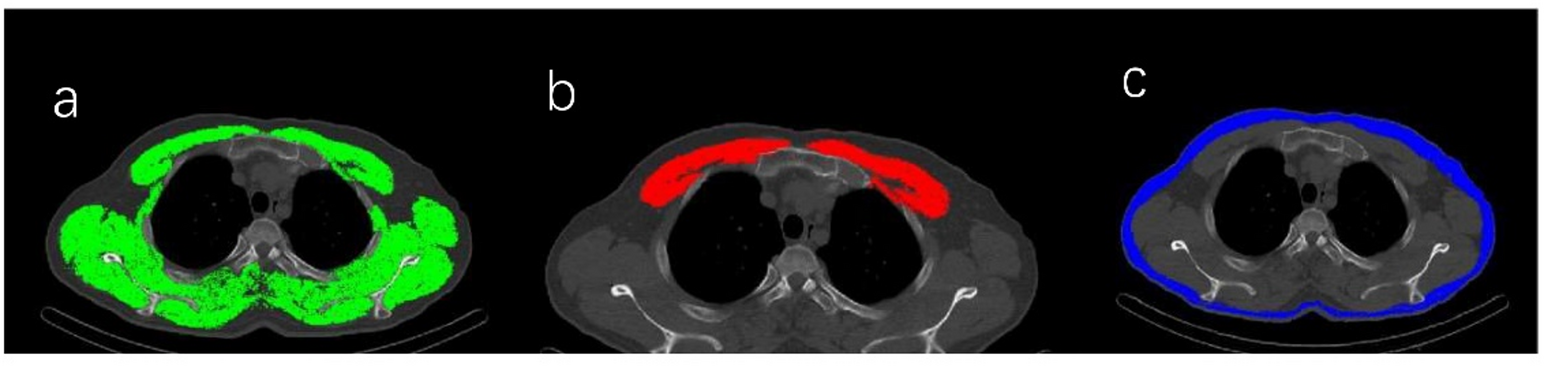

Fig. 2

Imaging findings in a 58-year-old man with recurrent pulmonary embolism (PE). (a) Skeletal muscle area (SMA) at the fourth thoracic vertebra: 187.1 cm².(b) Pectoralis muscle area (PMA): 37.16 cm².(c) Subcutaneous adipose tissue area (SATA): 48.94 cm².Follow-up computed tomography pulmonary angiography (CTPA) performed 19 months later revealed a new embolism.